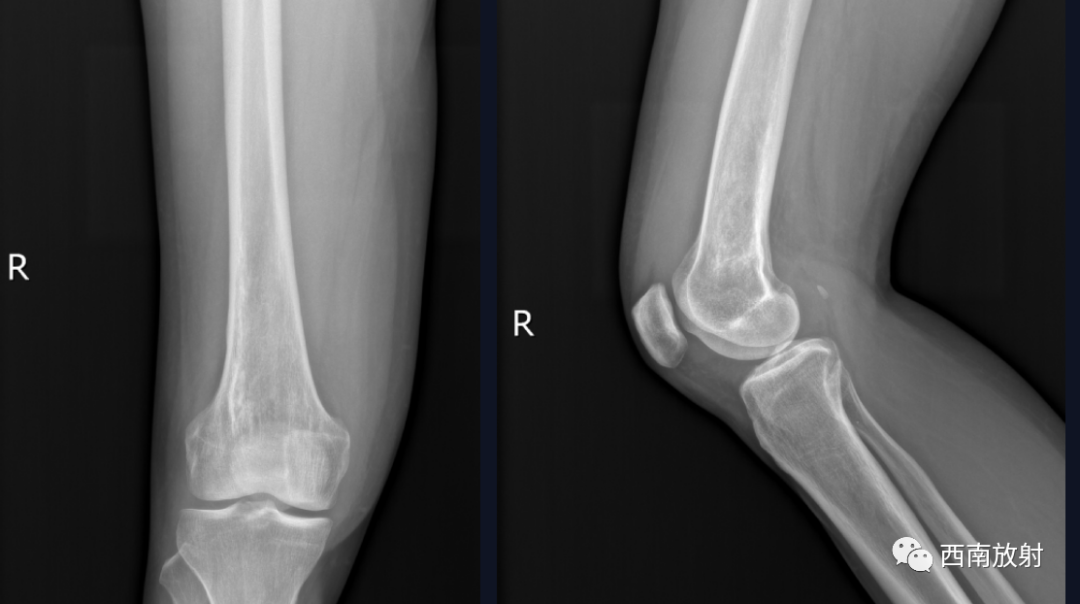

女,45岁。

主 诉:右膝关节疼痛16天,解黑便4天

现病史:患者于2021年8月17日开始出现右膝关节疼痛,无畏寒发热、恶心呕吐、咳嗽咳痰,无破溃、流脓,于8月20日在我院急诊科就诊,考虑关节炎,予口服双氯芬酸钠缓释片及泼尼松等药物治疗,无好转,随后转到天等县中医院就诊,予行右膝关节抽液及外敷中成药治疗(具体不详),4天前开始出现解黑便,每日1次,每次量约200g,伴有头晕、乏力,无腹痛、呕血、昏迷及呼吸困难等。今来院就诊,在门诊发现血压偏低,85/56mmHg,右膝关节抽出45ml的红色积液,右膝关节MRI示有骨髓炎,生命征不稳定,有转入我科指征,我科会诊后转入治疗。患者病后精神、睡眠差,未进食,大便如上述,小便色黄,量尚可,体重无明显变化。

诊断:慢性骨髓炎,周围软组织脓肿。

CT显示骨破坏、脓肿、死骨及骨膜增生、骨质增生硬化,呈骨小梁密度增高、模糊,髓腔密度增大、狭窄,皮质增厚。MRI显示早期骨髓内广泛分布的斑片异常信号,与邻近正常骨髓信号相比较,T1WI信号减低,T2WI信号增高,脂肪抑制T2WI 或STIR 等序列上病变显示更清楚,骨皮质周围软组织内呈弥漫分布的T1WI低信号及T2WI高信号影,边界模糊。出现骨膜反应,骨皮质不规则破坏,脓肿及死骨形成。